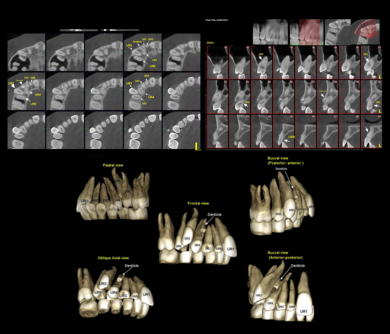

بعد از مشاوره نیاز به CBCT باشد

گاهی بعد از بررسی اولیه، ممکن است دندان نهفته، تحلیل استخوان یا شایط پیچیده تری وجود داشته باشه که برای تصمیم گیری دقیق تر دکتر نبی برای شما CBCT تجویز میکنن. نگران نباش؛ CBCT فقط در صورت نیاز واقعی درخواست میشه.

CBCT

CBCT تصویربرداری سه بعدی دقیق از استخوان و ریشه هاست و فقط در شرایط خاص تجویز میشه؛ مثل بررسی دندان نهفته یا تحلیل استخوان . این تصویر اطلاعات حیاتی برای درمانهای پیچیده فراهم میکنن.